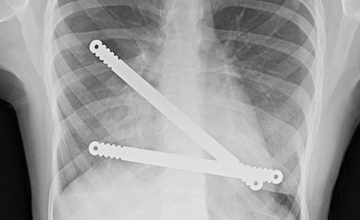

Pektus Ekskavatum

Pektus Ekskavatum (Kunduracı Göğsü)

Pektus ekskavatum sternum ve kıkırdak kostaların değişik derecelerde depresyonu ile karakterize bir ...